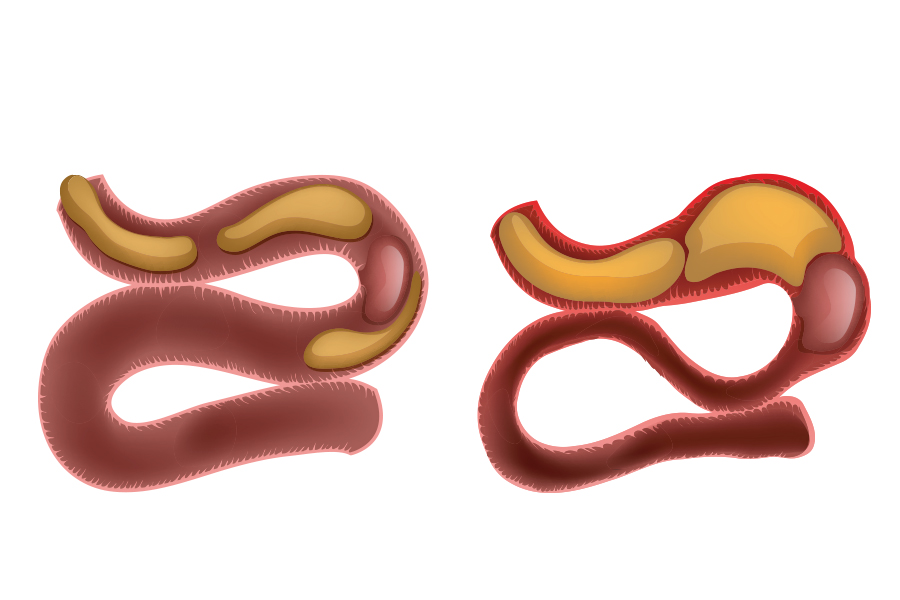

Иллюстрации и информация о симптомах острого кишечного непроходимости